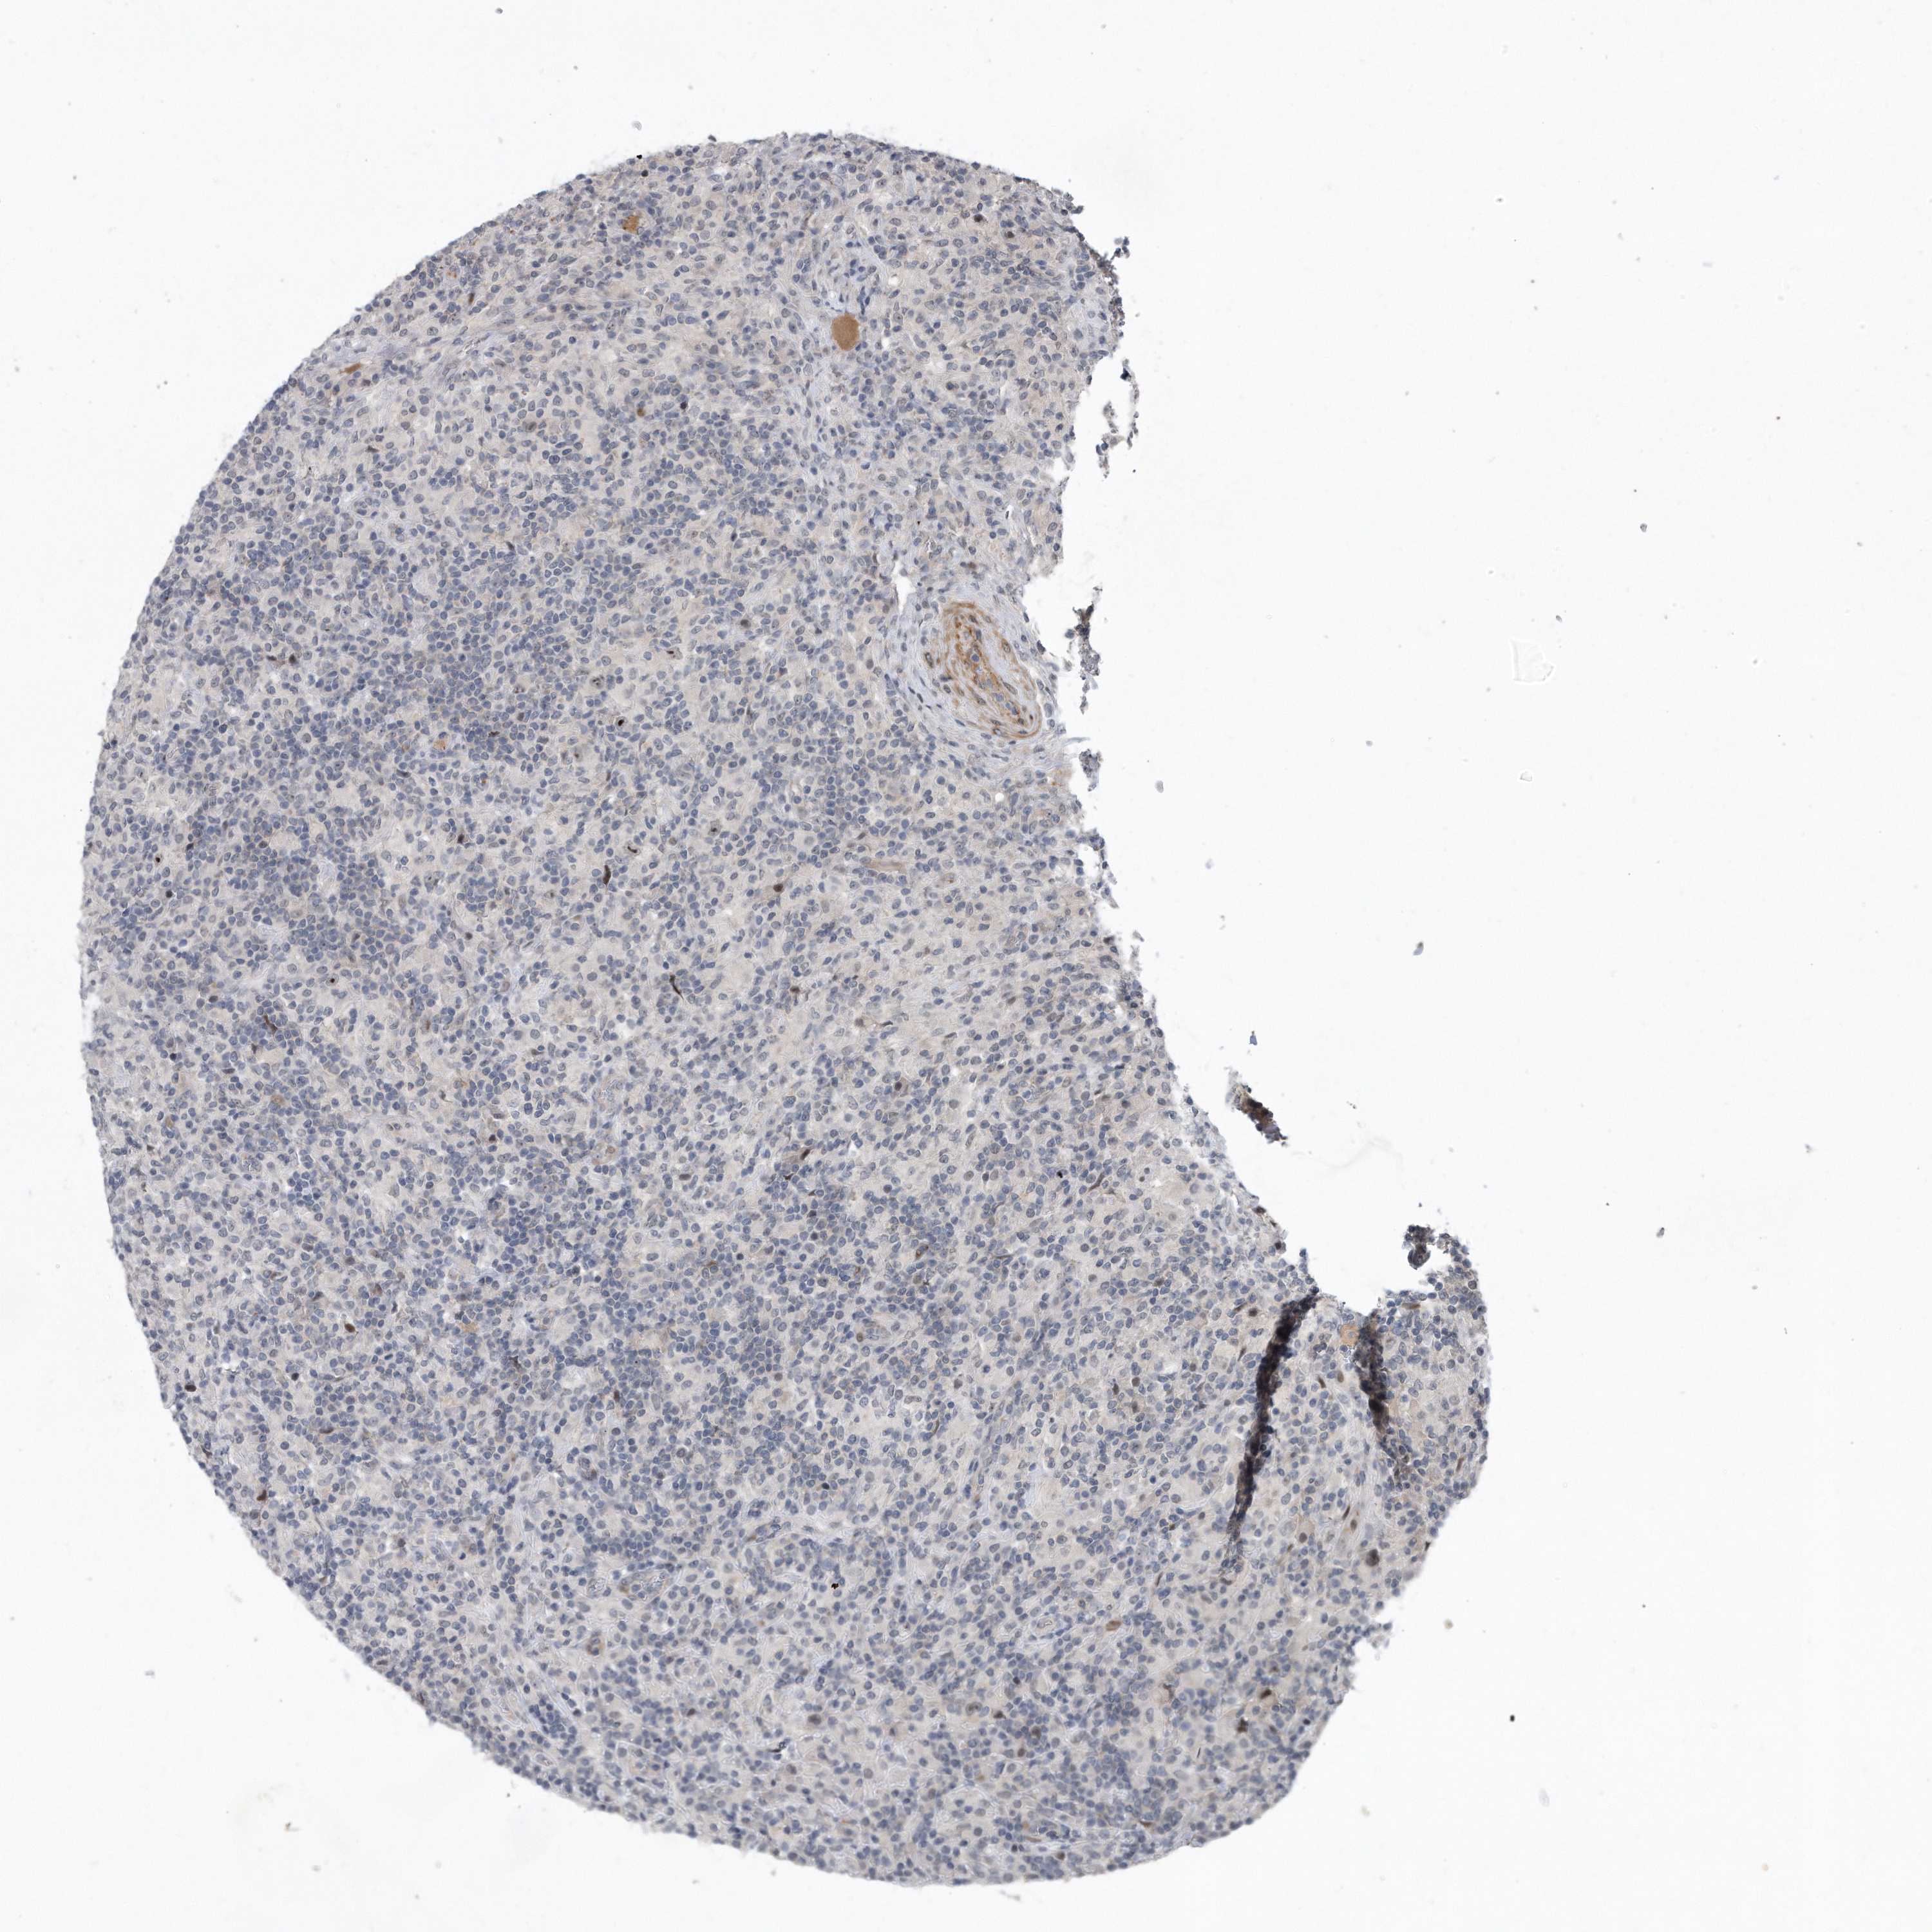

LYMPHOMA - Protein expressioni

A mouse-over function shows sample information and annotation data. Click on an image to view it in a full screen mode. Samples can be filtered based on level of antibody staining by selecting one or several of the following categories: high, medium, low and not detected. The assay and annotation is described here.

Antibody stainingi

Antibody staining in the annotated cell types in the current human tissue is reported as not detected, low, medium, or high, based on conventional immunohistochemistry profiling in selected tissues. This score is based on the combination of the staining intensity and fraction of stained cells.

Each image is clickable and will lead to virtual microscopy that enables deeper exploration of all samples and also displays staining intensity scores, fraction scores and subcellular localization as well as patient and tissue information for each sample.

Antibody HPA029888

Antibody HPA029889

Antibody HPA029890

Hodgkin's disease, NOS

Malignant lymphoma, non-Hodgkin's type, High grade

Malignant lymphoma, non-Hodgkin's type, Low grade